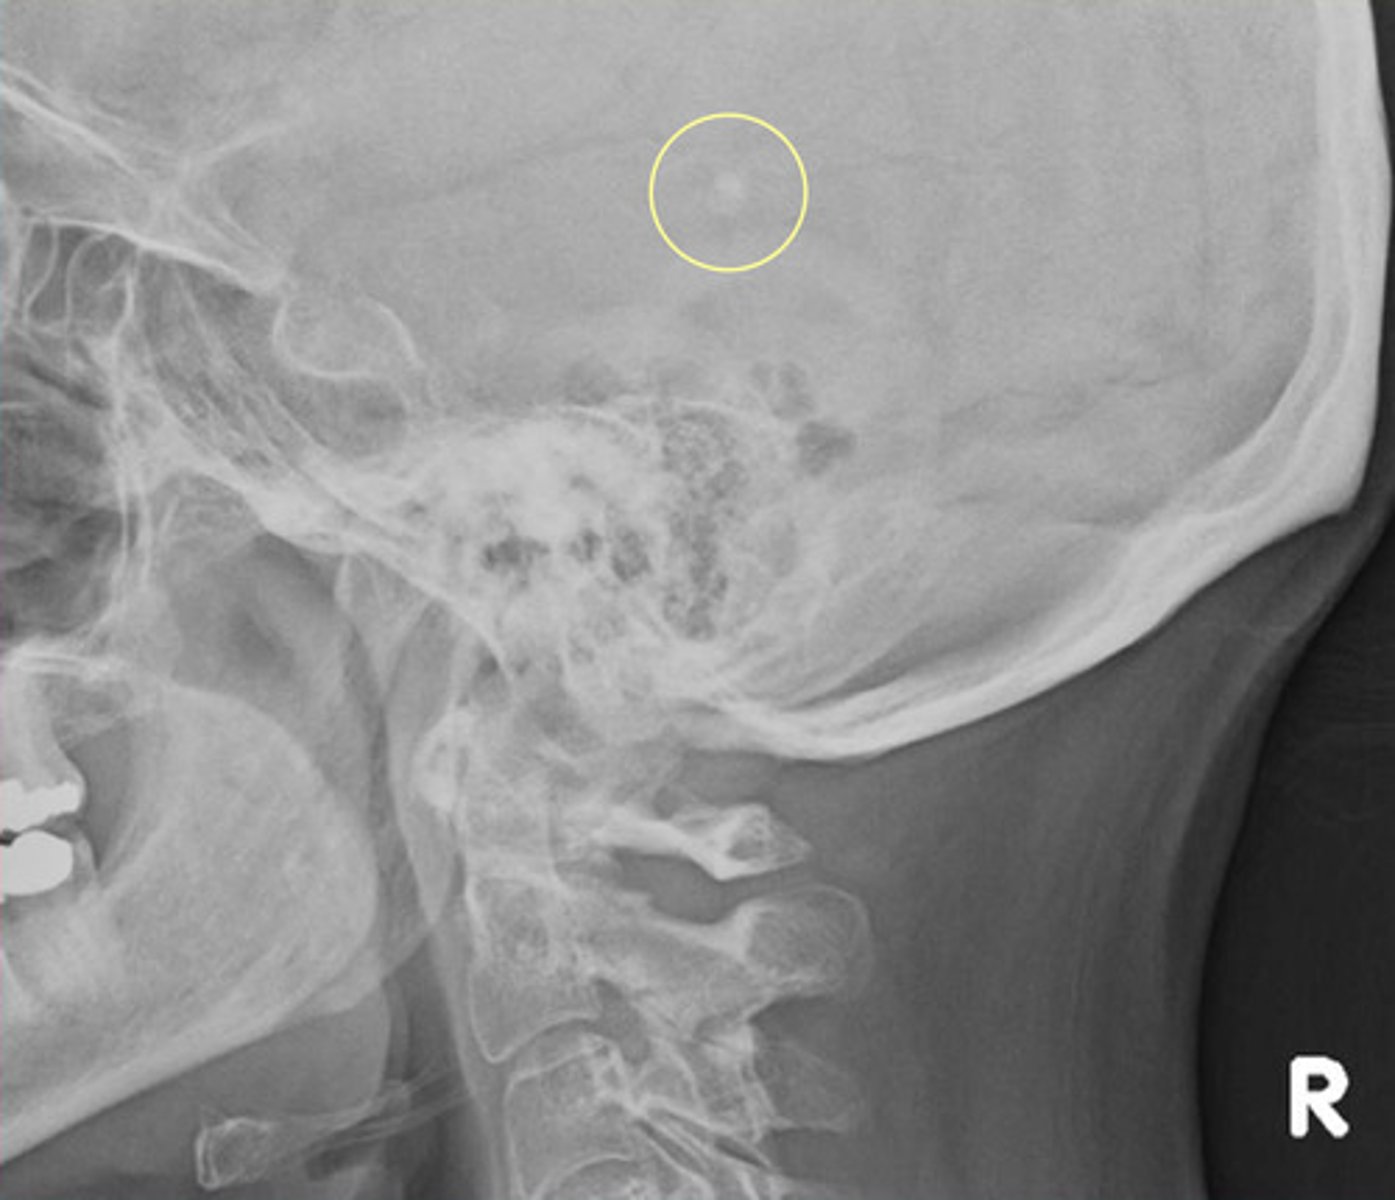

Pineal Gland Calcification

Physiological calcification in about 50% of the population

What age should we suspect a neoplasm instead of pineal gland calcification?

< 6 years it is very rare so suspect a neoplasm (pinealoma)

What is the maximum size of pineal gland calcification?

Should not exceed 10 mm